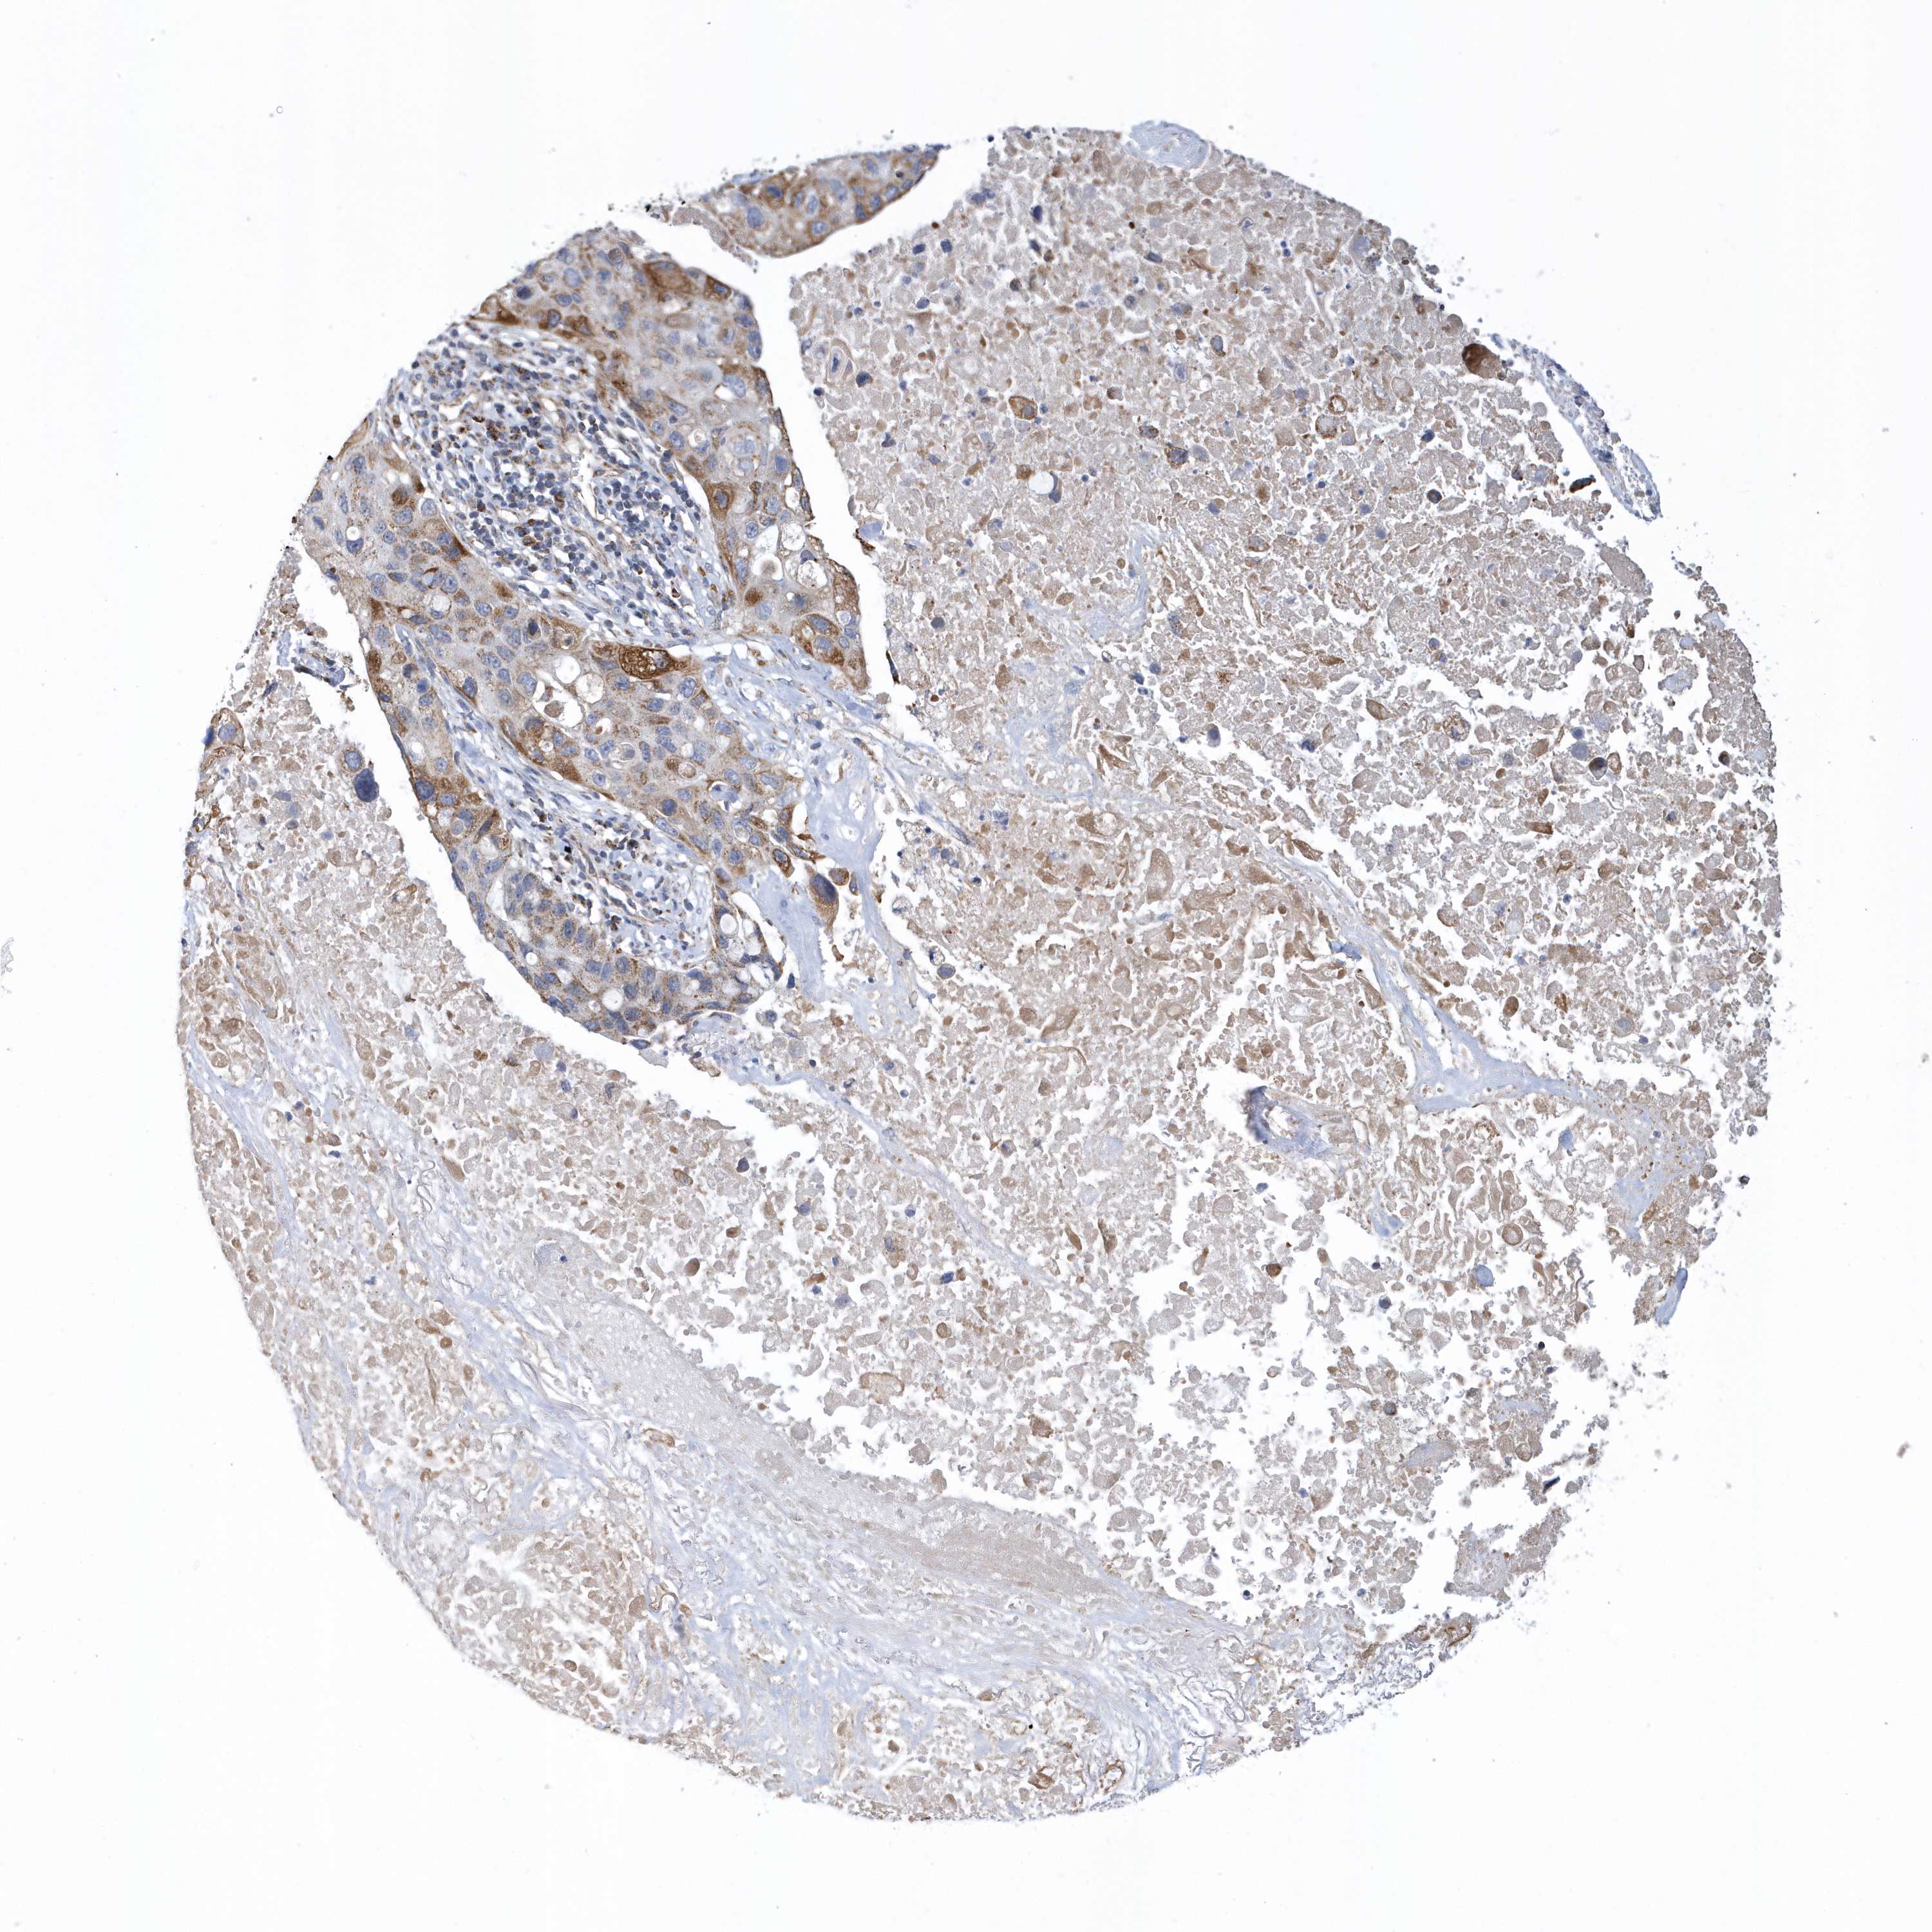

LUNG SQUAMOUS CELL CARCINOMA (TCGA) - Interactive survival scatter ploti

The Survival Scatter plot shows the clinical status (i.e. dead or alive) for all individuals in the patient cohort, based on the same data that underlies the corresponding Kaplan-Meier plots. Patients that are alive at last time for follow-up are shown in blue and patients who have died during the study are shown in red.

The x-axis shows the expression levels (FPKM) of the investigated gene in the tumor tissue at the time of diagnosis. The y-axis shows the follow-up time after diagnosis (years). Both axes are complimented with kernel density curves demonstrating the data density over the axes. The top density plot shows the expression levels (FPKM) distribution among dead (red) and alive patients (blue). The right density plot shows the data density of the survived years of dead patients with high and low expression levels respectively, stratified using the cutoff indicated by the vertical dashed line through the Survival Scatter plot. This cutoff is automatically defined based on the FPKM cutoff that minimizes the p-score. The cutoff can be changed by dragging the vertical line or by entering a cutoff value in the square labeled "Current cut-off".

Under the Survival Scatter plot the p-score landscape (black curve; left axis) is shown together with dead median separation (red curve; right axis). Dead median separation is the difference in median mRNA expression between patients who have died with high and low expression, respectively. It is calculated as follows: median FPKM expression of dead patients with high expression - median FPKM expression of dead patients with low expression. This is intended to aid the user in visually exploring custom cutoffs and the associated p-scores and dead median separation.

Individual patient data is displayed and can be filtered by clicking on one or more of the category buttons on the top of the page. Categories describing expression level and patient information include: high, low, alive, dead, female, male and tumor stages. The scale of the x-axis can be toggled between linear and log-scale by clicking on the "x log" button. Mouse-over function shows TCGA ID, patient information and mRNA expression (FPKM) for each patient.

& Survival analysisi

Kaplan-Meier plots summarize results from analysis of correlation between mRNA expression level and patient survival. Patients were divided based on level of expression into one of the two groups "low" (under cut off) or "high" (over cut off). X-axis shows time for survival (years) and y-axis shows the probability of survival, where 1.0 corresponds to 100 percent.

VWA5B2 is not prognostic in Lung Squamous Cell Carcinoma (TCGA)

Stage:

Survival analysis

P scorei

Log-rank P value for Kaplan-Meier plot showing results from analysis of correlation between mRNA expression level and patient survival.

N/A

5-year survival highi

5-year survival for patients with higher expression than the expression cutoff.

For melanoma and glioma, 3-year survival is shown.

5-year survival lowi

5-year survival for patients with lower expression than the expression cutoff.

TCGA RNA samplesi

RNA-seq data is reported as average FPKM (number Fragments Per Kilobase of exon per Million reads), generated by the The Cancer Genome Atlas (TCGA) .

Normal distribution across the dataset is visualized with box plots, shown as median and 25th and 75th percentiles. Points are displayed as outliers if they are above or below 1.5 times the interquartile range. FPKM values of the individual samples are presented next to the box plot.

Average pTPM 0.4

Number of samples 489